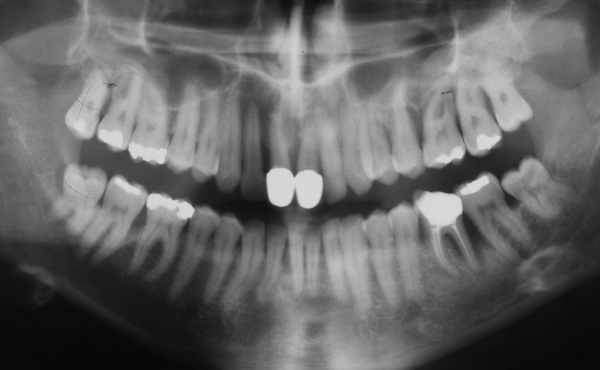

Der Erstbefund zeigte eine generalisiert entzündliche marginale Gingiva mit generalisierter Blutungsneigung bei Sondierung. Die approximalen Sondiertiefen waren durchgehend erhöht und betrugen im Molarenbereich bis zu 12 mm (s. Abb. 4). Es lagen multiple Zahnlockerungen vor, eine Zahnlockerung des Grades II zeigte sich an den Zähnen 11, 25, 26, 38, 37, 47; Grad III am Zahn 24. Harte Beläge in der Unterkieferfront, generalisiert weiche Beläge (API 62 %). Wurzelkaries an 24. Suffiziente Brückenversorgung im I. Quadranten. Die Panoramaschichtaufnahme von Juni 1998 (s. Abb. 4) zeigt einen generalisierten horizontalen Knochenabbau mit vertikalen Einbrüchen in regio 17, 25, 37 und 47. Interradikuläre Aufhellungen im Sinne einer Furkationsbeteiligung an 17, 26, 38, 37 und 47. Via falsa an 24.